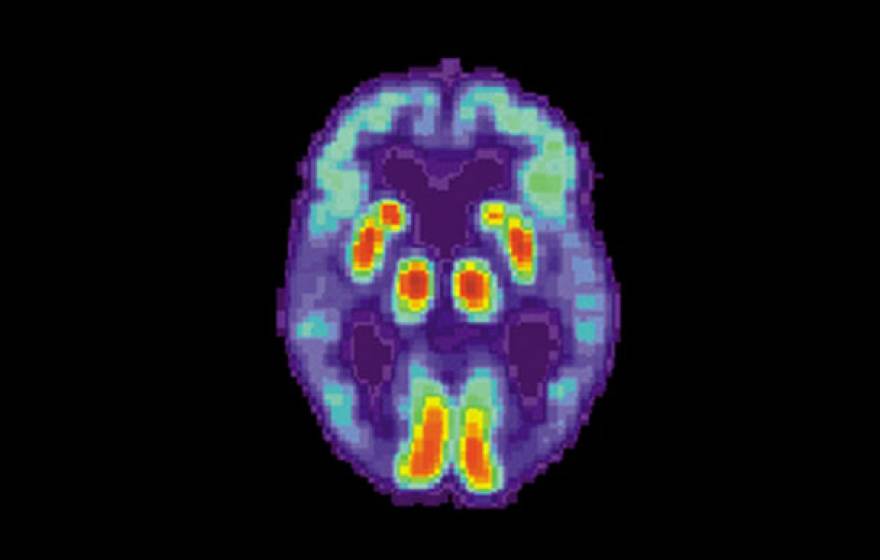

Artificial intelligence can detect Alzheimer’s disease in brain scans 6 years before a diagnosis

A machine-learning algorithm diagnosed early-stage Alzheimer’s disease using a common PET scan.